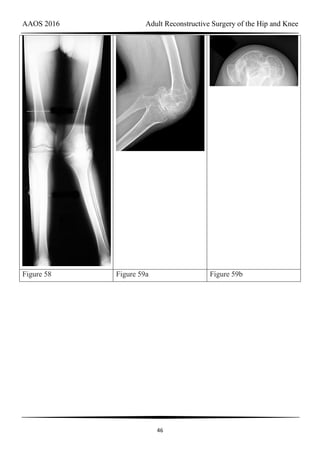

Figure 58 Figure 59a Figure 59b

RESPONSES FOR QUESTIONS 58 THROUGH 62

Total knee arthroplasty (TKA) is performed to address each condition shown in Figures

58 through 62b. Which complication is most commonly associated with each image?

Question 58 of 200

Figure 58

1- Nerve palsy

2- Skin necrosis

3- Flexion instability

4- Patellar instability

5- Anterior knee pain

6- Malalignment

PREFERRED RESPONSE: 1- Nerve palsy

Question 59 of 200

Figure 59a and Figure 59b

AAOS 2016 Adult Reconstructive Surgery of the Hip and Knee

49

PREFERRED RESPONSE: 4- Patellar instability

DISCUSSION

Figure 58 reveals a posttraumatic valgus deformity. Correction of valgus with lateral soft-

tissue release places tension on the peroneal nerve, resulting in an increased risk for nerve

palsy. Figures 59a (lateral view) and 59b (Merchant view) illustrate juvenile rheumatoid

arthritis with tibiofibular fusion and lateral patellar dislocation. Chronic patellar dislocation is

associated with contracture of the lateral retinacular soft tissues and increased risk for patellar

subluxation or dislocation after TKA. Extensor mechanism realignment, possibly including

tibial tubercle osteotomy and/or proximal soft-tissue realignment, may be required during

TKA to centralize the extensor mechanism. Figures 60a (anteroposterior [AP] view) and 60b

(lateral view) reveal a fused knee in full extension.